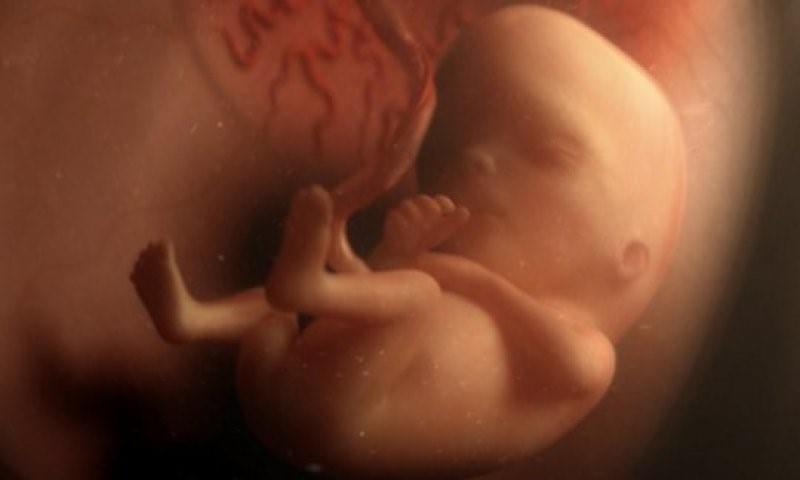

В течение трех недель клетки образуют малюсенький шарик (эмбрион). Формируются первые нервные клетки. После восьмой недели и до рождения будущего ребенка правильно называть плодом.

Вокруг плодного яйца образуется водонепроницаемая оболочка с жидкостью (амниотический мешок), защищая растущий эмбрион. Одновременно развивается плацента – округлый плоский орган, через который плод получает питательные вещества от матери.

На голове появляются небольшие складки кожи в районе ушей, глаза. Формируются крошечные ручки, ножки, пальцы.

Полная сформирована нервная трубка (головной, спинной мозг и другие элементы центральной нервной системы). Начинают развиваться пищеварительный тракт и органы чувств. Хрящи заменяются костями.

Появляется сердцебиение, а голова ребенка гораздо больше по отношению к остальному телу.